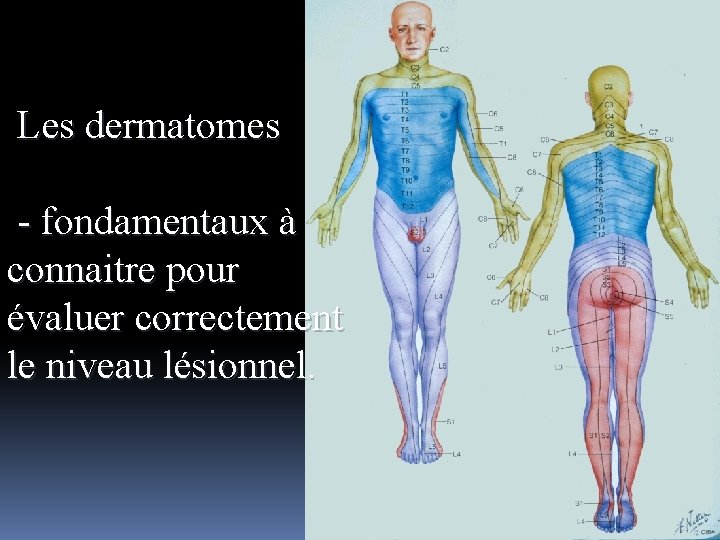

Repères anatomiques: T 4 mamelon T 9 ombilic L 1 pli de l’aine

Les dermatomes - fondamentaux à connaitre pour évaluer correctement le niveau lésionnel.